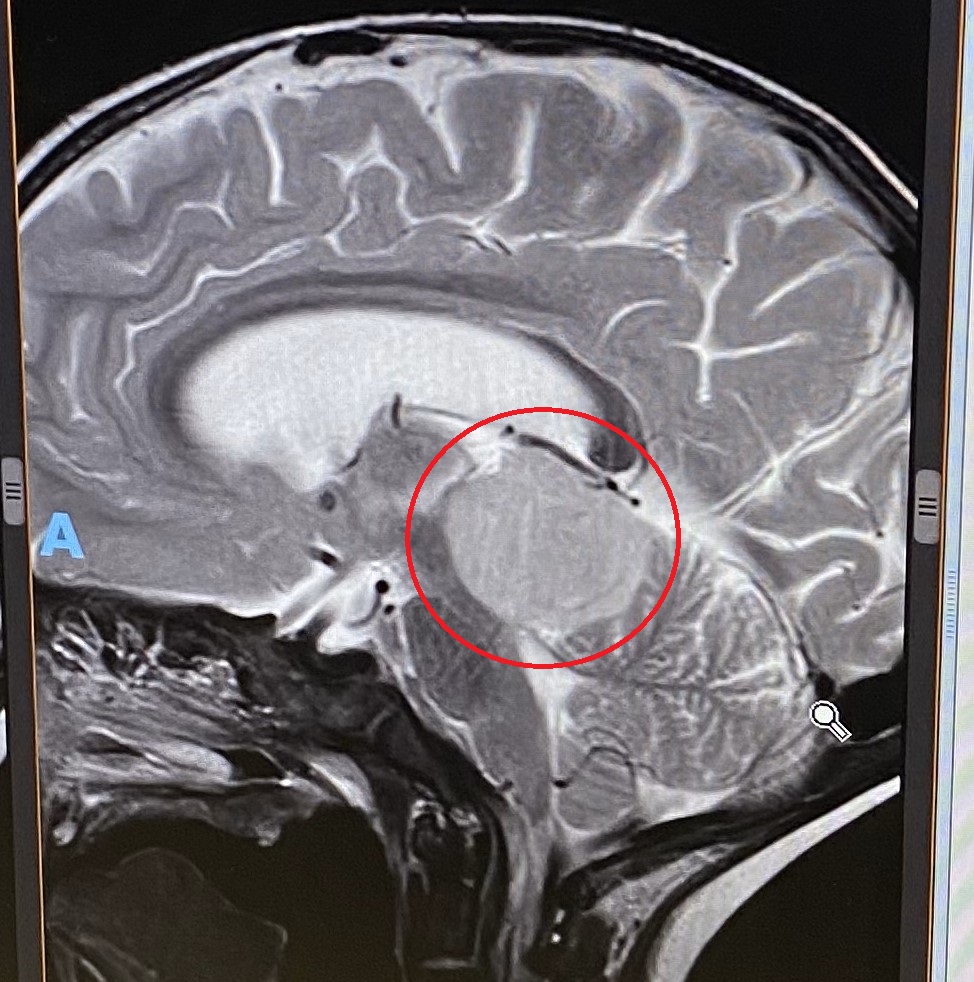

And here is a little reminder of the miracle two years ago today – an MRI image of Eloise’s brain on the morning with the tumour (circled), before it was removed. (Note: the cursor is placed where the neurosurgeon entered to get to the tumour!)